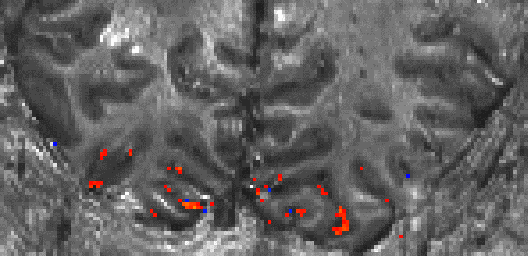

1.) Inflow

VASO is an inversion-recovery sequence, and is thus very similar to an ASL-CBF sequence. Similarly, like in ASL, VASO can therefore have contaminations of inflowing fresh (uninverted) blood. E.g. in areas of very short arterial arrival times (e.g. large arteries), fresh blood can flow into the imaging region. The voxels that are effected by this inflow, are usually very bright in the raw VASO signal and can be easily identified. During activity increase, more of this fresh blood flows into the imaging regions and functionally increases the resulting VASO signal dependent on the CBF increase. Since VASO is a negative CBV contrast, this inflow effect counteracts the CBV related VASO signal change and canmask negative signal change.

This effect of inflow-related negative voxels is easily identified and hence can be accounted for by excluding these voxels from the analysis. The effect can be removed form the acquisition side by choosing shorter inversion times (at the cost of SNR). Since this effect is usually only happening in pial vessels, it can be ignored for analyses pipelines that focus on GM voxels only.